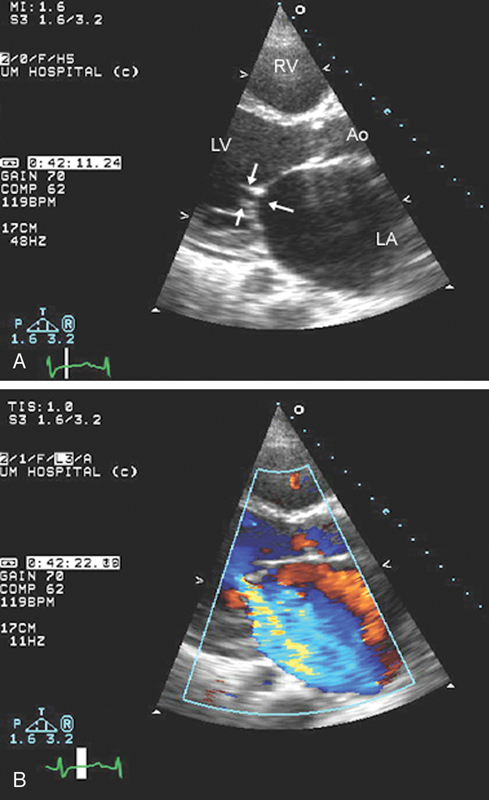

فحوصات تشخيصية لبعض امراض القلب والشرايين التاجية